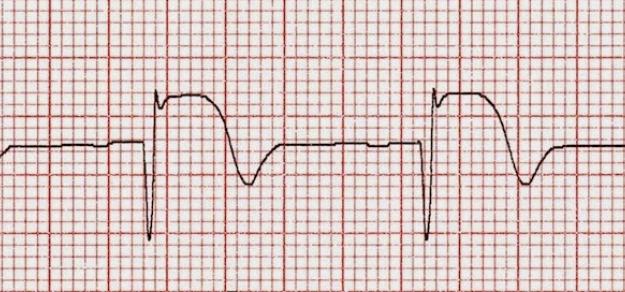

Pacientes con infarto agudo derivados a centros de hemodinamia en Argentina

Uno de cada tres pacientes es derivado para reperfusión miocárdica, pero los derivados tienen menor probabilidad de recibir tratamiento de reperfusión y menor utilización de angioplastia primaria. Una mejor articulación de las redes podría mejorar el acceso y disminuir la morbimortalidad. Revista Argentina de Cardiología, 2017 Nº 2